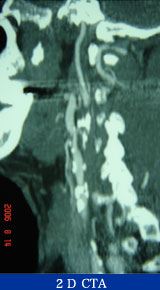

67歳 男性

検診異常

平成18年5月検診にて胸部大動脈瘤を指摘。

7月当院紹介受診。

65歳 胃癌 → EMR

高血圧(+) 糖尿病(−) 喫煙歴(−)

Gore社TAG stent留置術

胸部CT検査

腹部CTA検査